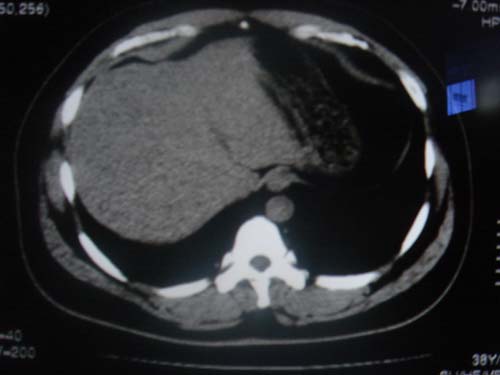

患者 男 40 右上腹不适 有胆囊息肉病史2年

本例就是胆囊比较大,内密度不很均匀,疑有砂砾状结石,未见息肉以及其他异常。

肝脏增大,

最后二副图像示胆囊壁增厚,与肝分界欠清,建议强化ct或磁共振

片中示肝脏的ct值低于脾脏,肝脏右叶外缘部份凹凸不平,考虑脂肪肝,肝硬化可能。结合其检查如b超或ct增强检查。

胆囊未见明显异常,肝脏密度似比脾脏密度低,测量一下ct值排除一下脂肪肝.当然做一下增强或mr就更好了.

肝右叶密度不均,脾大。强烈要求增强扫描除外浸润型肝癌。

肝大   密度降低  脾大  脂肪肝?